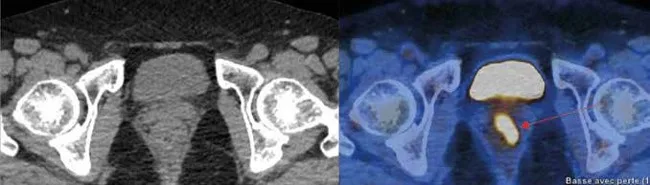

Évaluation de la réponse thérapeutique et diagnostic de la récidive

La récidive du cancer du canal anal survient chez environ 30 % des patients, 2 ans après la fin du traitement et plus particulièrement chez les patients ayant un stade T initial élevé. Il s’agit le plus souvent de récidives loco-régionales (75 % des cas), suivies des récidives au niveau des régions pré-sacrées et ganglionnaires iliaques (21 %) et plus rarement d’une récidive au niveau des aires ganglionnaires inguinales (4 %) [23]. Les différentes études ont retrouvé une excellente valeur prédictive négative de la TEP au FDG dans l’évaluation de la maladie résiduelle ou la détection de la récidive du cancer du canal anal [24,25]. La grande majorité des récidives locale ou loco-régionale sont traitées par amputation abdomino- périnéale. L’étude Nationale multicentrique récemment publiée, retrouve la valeur pronostique de la TEP FDG sur la survie sans récidive, la survie post-chirurgie et la survie globale [26]. Les auteurs soulignent que la TEP FDG pourrait être recommandée 4 à 6 mois après la fin de la radio- chimiothérapie chez les patients avec une tumeur localement avancée.

Dans ce contexte d’évaluation thérapeutique après la fin de traitement (4–6 mois après la fin de la radiothérapie ou radio-chimiothérapie), du fait de cette excellente valeur prédictive négative, la TEP peut permettre d’éviter les biopsies en cas de réponse métabolique complète. En effet, les biopsies sont dans ce contexte, non dénuées de complications, surtout après curiethérapie interstitielle, dans un tissu fibreux peu vascularisé, la complication principale étant la nécrose locorégionale qui imposerait une sanction chirurgicale radicale. La négativité de la TEP au FDG réalisée au moins 12 semaines après la fin de traitement d’un cancer du canal anal est corrélée à une meilleure survie sans récidive.

Plusieurs auteurs insistent sur le risque de faux positifs de la TEP au niveau local lorsqu’elle est réalisée trop précocement (un mois) par rapport à la fin du traitement de radio-chimiothérapie, suggérant l’importance de respecter un délai minimum d’au moins 12 semaines après la fin du traitement pour la réaliser. Par ailleurs, dans certains cas de tumeur initiale volumineuse, la lésion peut régresser lentement (parfois jusqu’à 26 semaines après la fin de la radiothérapie).

La TEP FDG présente de bonnes valeurs de sensibilité, spécificité, valeur prédictive positive et en particulier une excellente valeur prédictive négative pour la détection de la maladie résiduelle ou de la récidive du cancer du canal anal.

La TEP au FDG peut être proposée pour l’évaluation thérapeutique à la fin du traitement de radiochimiothérapie dans le cancer du canal anal.